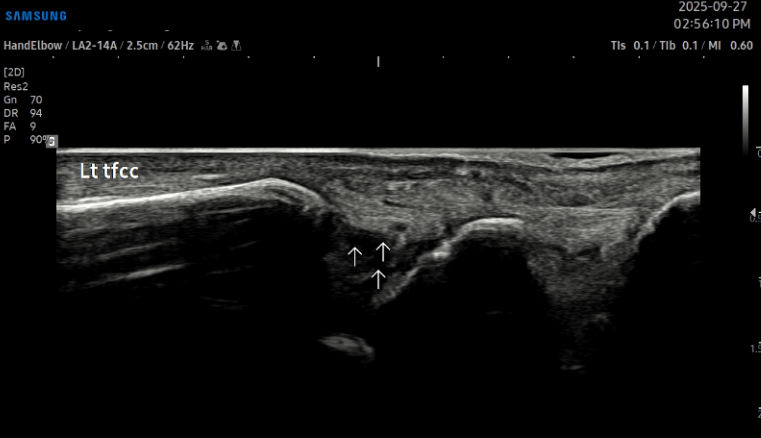

치료 전 (TFCC)

치료 후 (TFCC)\

- 치료기간 : 25 . 8 . 5 ~ 25 . 10 . 28

- 치료횟수 : 4 cycle(20) 회